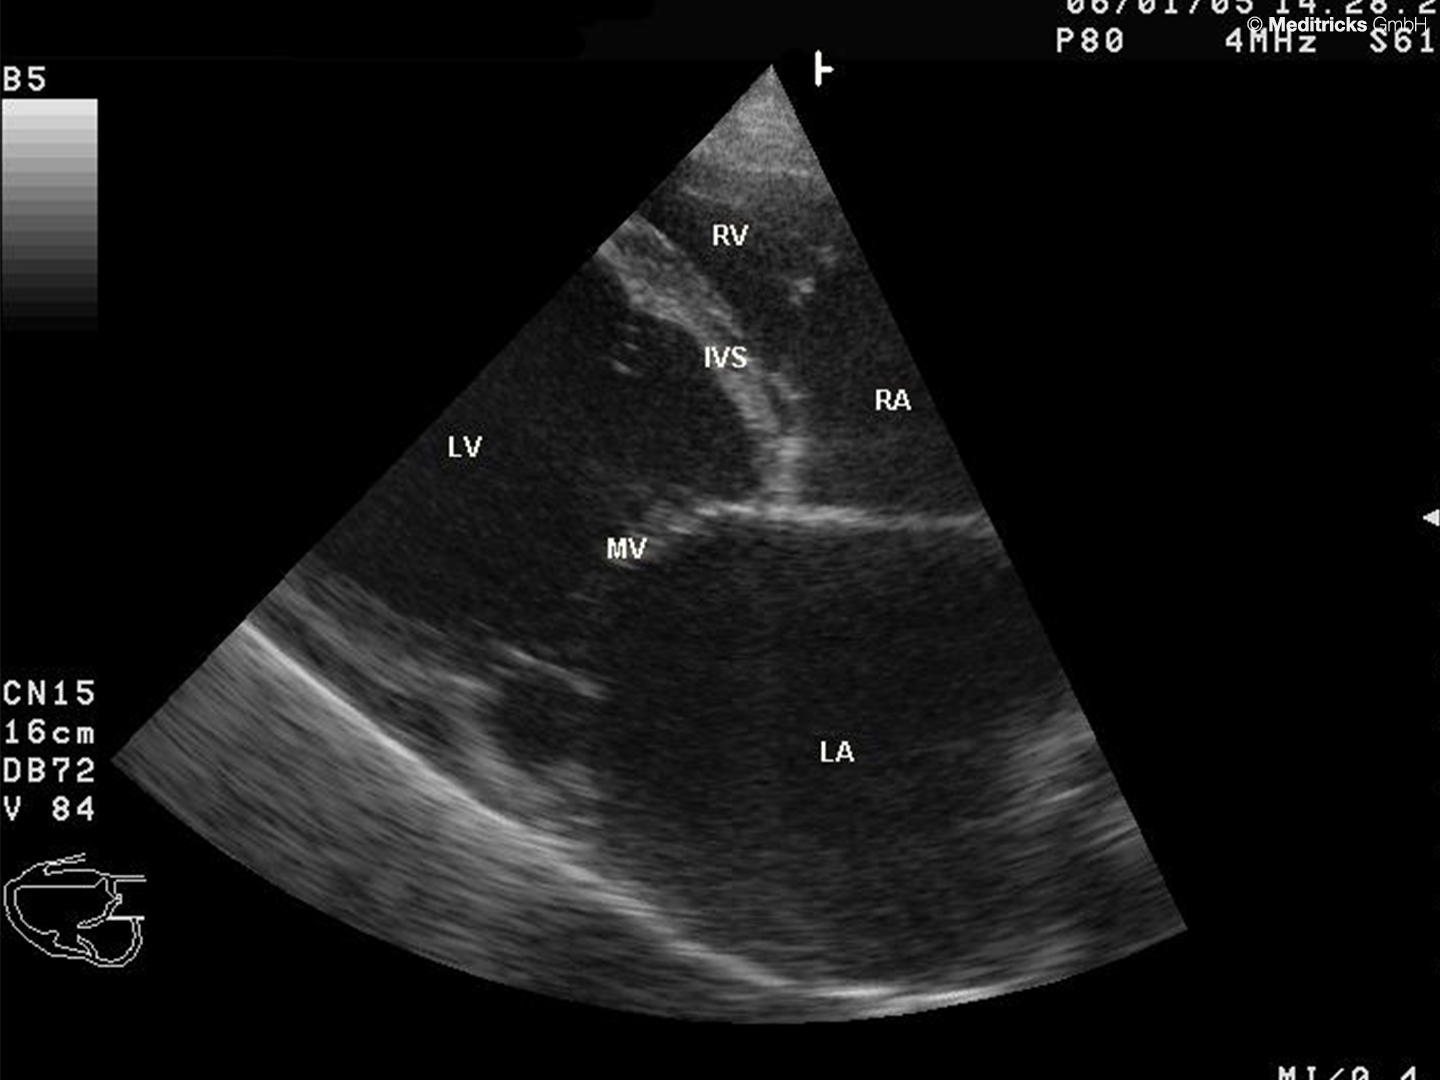

Mit LA beschriftet der riesige linke Vorhof (left atrium). Eine Vorhofdilatation (hier bei dilatativer Kardiomyopathie) gilt als Risikofaktor fürs Vorhofflimmern, ist also oft damit vergesellschaftet.

Quelle: CC BY-SA 3.0 "Dilated cardiomyopathy B-Mode". Wikimedia Commons. User: Kalumet

Vorhofdilatation beim Vorhofflimmern - Mit LA beschriftet der riesige linke Vorhof (left atrium). Eine Vorhofdilatation (hier bei dilatativer Kardiomyopathie) gilt als Risikofaktor fürs Vorhofflimmern, ist also oft damit vergesellschaftet.

Oft ist eine Vorhofdilatation Abb. 858 die Folge einer Volumen- oder Druckbelastung des Herzens. Das kann eine Ursache für VHF sein.

Oft ist eine Vorhofdilatation [[Abb. 8588]] die Folge einer Volumen- oder Druckbelastung des Herzens. Das kann eine Ursache für VHF sein.